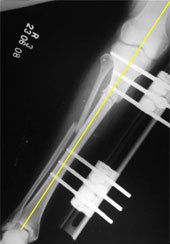

The x-ray picture here shows the fibular and tibial osteotomies.

Both the deformities, angulation and rotation were corrected acutely on the operating table. Since the osteotomy was made at the level of CORA there was no translation at the osteotomy site.

The bone is held in the corrected position with a LRS fixator.

The corrected bone axis is shown by the yellow line. |